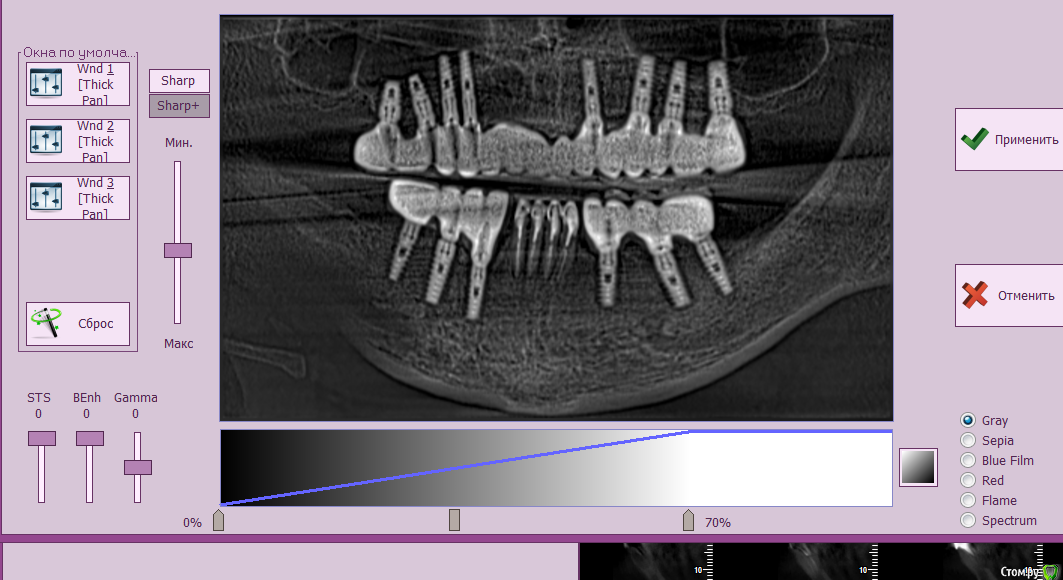

Irouil Опубликовано 13 марта, 2018 Поделиться Опубликовано 13 марта, 2018 Может быть вопросы только в правой пазухе. С левой стороны хоть немного торчат в пазуху, но причиной проблем не являются сейчас Надо сделать такие же скрины, только ползунок поднять чтобы верхняя челюсть видна была 1 Ссылка на комментарий

Zztop90 Опубликовано 13 марта, 2018 Автор Поделиться Опубликовано 13 марта, 2018 (изменено) Может быть вопросы только в правой пазухе. С левой стороны хоть немного торчат в пазуху, но причиной проблем не являются сейчас Надо сделать такие же скрины, только ползунок поднять чтобы верхняя челюсть видна былаНаверное я не так понял, какой ползунок, впервые просто с такими программами сталкиваюсь. на всякий случай поднял оба. Там еще есть 2 режима, MPR и 3D (Не доступен) Изменено 13 марта, 2018 пользователем Zztop90 Ссылка на комментарий

Irouil Опубликовано 13 марта, 2018 Поделиться Опубликовано 13 марта, 2018 Нет, только один, тот что слева наверху и то, наверное, не до конца. Но вообще я Ваши первые скрины пересмотрел... Не вижу никаких срочных проблем в пазухе. Из-за того, что есть на снимках, я бы не предлагал ничего снять. Раз в год снимки переделывать и контролировать прогресс. Там где оголяется хороший парадонтолог может все вывести на надёжный прогноз. Учитывая монолитность конструкции, углы установки почти не помеха. С пазухами если будут проблемы, то имплантаты тут не причинами, а только оттягчяющими обстоятельствами могут быть. Устранив причину (раскрыв соустья пазух) Вы не вспомните про имплантаты. В общем, с приложенными данными, удалять ничего не рекомендую 2 Ссылка на комментарий

Zztop90 Опубликовано 13 марта, 2018 Автор Поделиться Опубликовано 13 марта, 2018 Нет, только один, тот что слева наверху и то, наверное, не до конца. Но вообще я Ваши первые скрины пересмотрел... Не вижу никаких срочных проблем в пазухе. Из-за того, что есть на снимках, я бы не предлагал ничего снять. Раз в год снимки переделывать и контролировать прогресс. Там где оголяется хороший парадонтолог может все вывести на надёжный прогноз. Учитывая монолитность конструкции, углы установки почти не помеха. С пазухами если будут проблемы, то имплантаты тут не причинами, а только оттягчяющими обстоятельствами могут быть. Устранив причину (раскрыв соустья пазух) Вы не вспомните про имплантаты. В общем, с приложенными данными, удалять ничего не рекомендуюВроде понял, при подъеме правого ползунка прицел двигается вправо на верхней челюсти: Вы меня обнадежили, конечно, так как проходить все с 0 опять- для меня хуже пытки. Вдвойне благодарю вас за потраченное время в свой день рождения, поздравляю вас с праздником) 1 Ссылка на комментарий